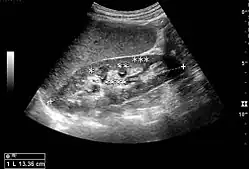

The hydronephrosis is typically graded visually and can be divided into five categories going from a slight expansion of the renal pelvis to end-stage hydronephrosis with cortical thinning (Figure 15). The evaluation of hydronephrosis can also include measures of calyces at the level of the neck in the longitudinal scan plane, of the dilated renal pelvis in the transverse scan plane and the cortical thickness, as explained previously (Figure 16 and Figure 17).[1]

Figure 18. Renal stone located at the pyeloureteric junction with accompanying hydronephrosis.[1]

With US, larger stones (>5–7 mm) within the kidney, i.e., in the calyces, the pelvis and the pyeloureteric junction, can be differentiated, especially in the cases with accompanying hydronephrosis (Figure 18 and Figure 19). Hyperechoic stones are seen with accompanying posterior shadowing. Additional twinkling artifacts below the stone can often be seen using Doppler US. Large stones filling the entire collecting system are called coral stones or staghorn calculi and are easily visualized with US (Figure 20). Stones in the ureters are usually not visualized with US due to the air-filled intestines obscuring the insonation window. However, ureteral stones near the ostium can be visualized with a scan position over the bladder. An exam of the ureteric orifices and the excretion of urine to the bladder can be performed by inspecting the ureteric jets in the bladder with color Doppler US.